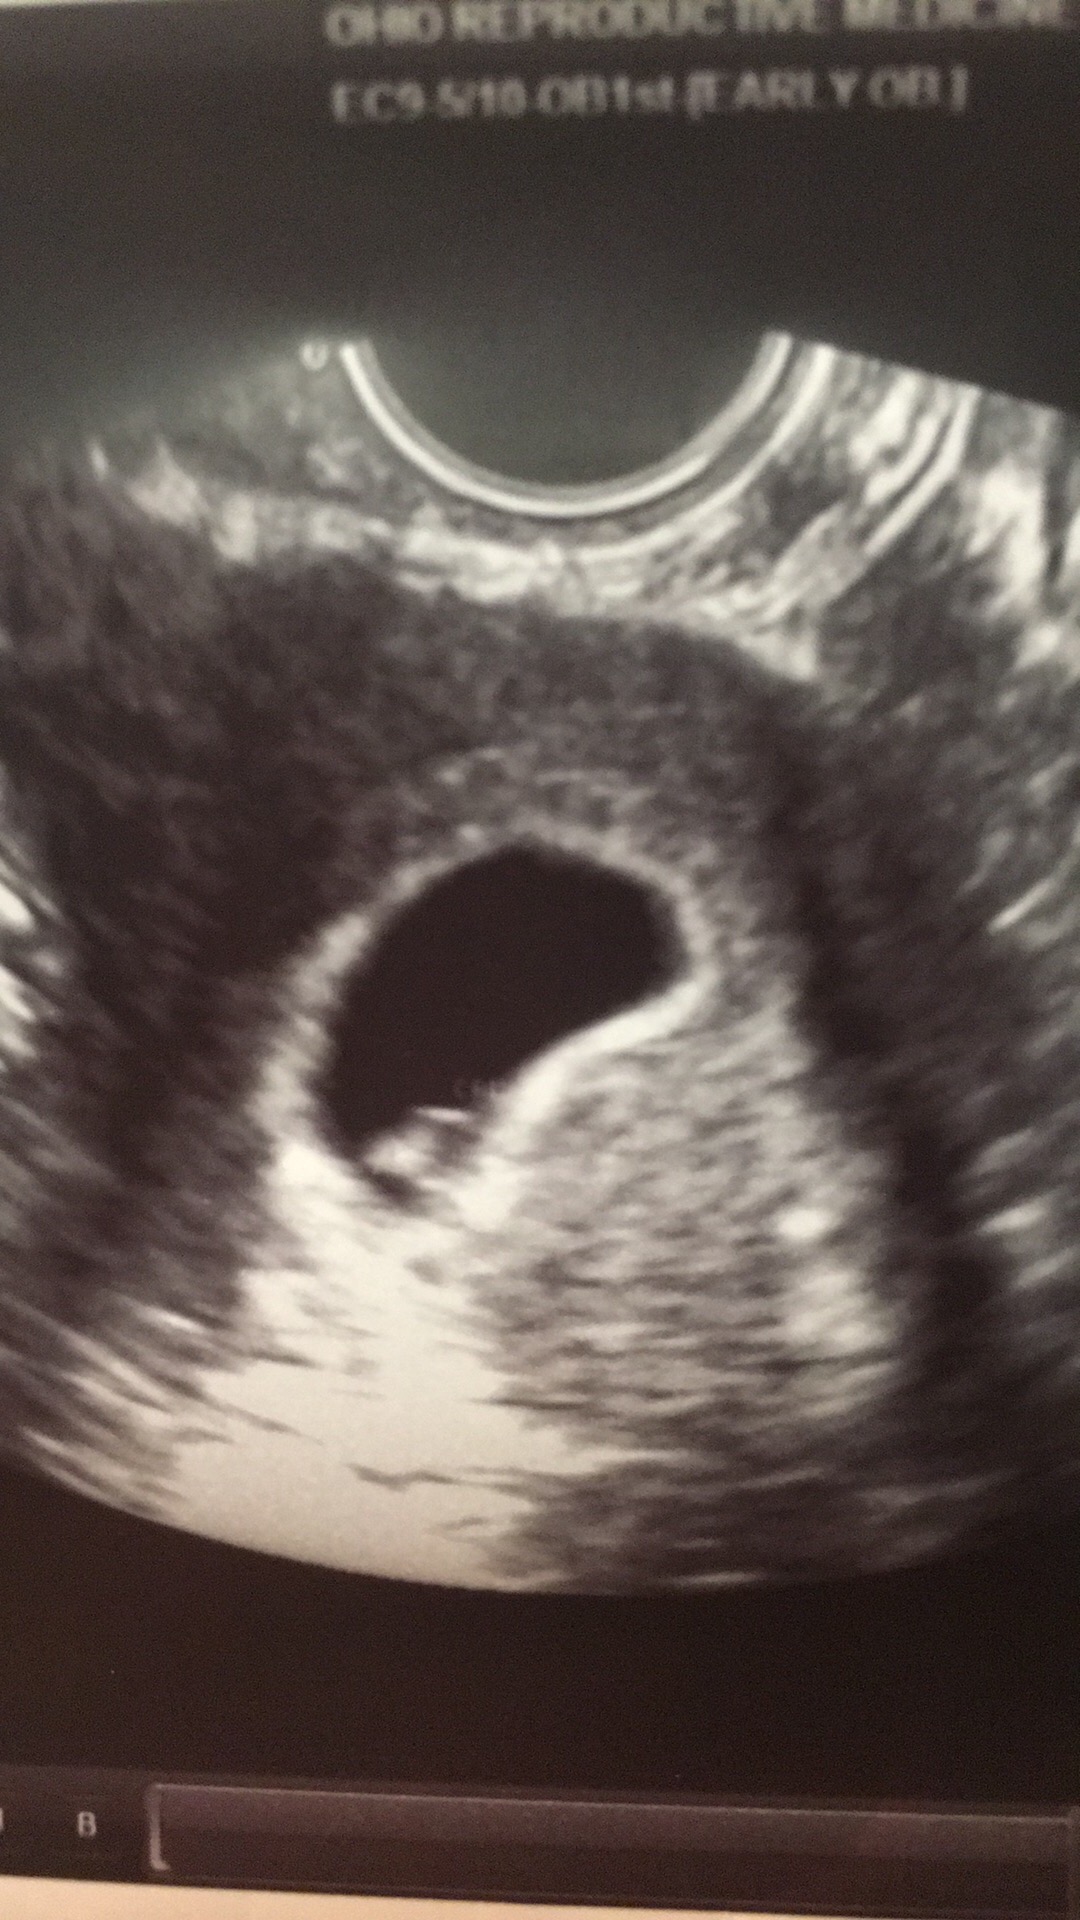

Heres my other thing. The red, dr said its pools of blood and unsure if its a sch. He told me to come back june 8, and we would see whats up. We only got to see the baby for a few seconds.

Any input? He wouldnt answer if its an sch, just said to keep an eye on blood.